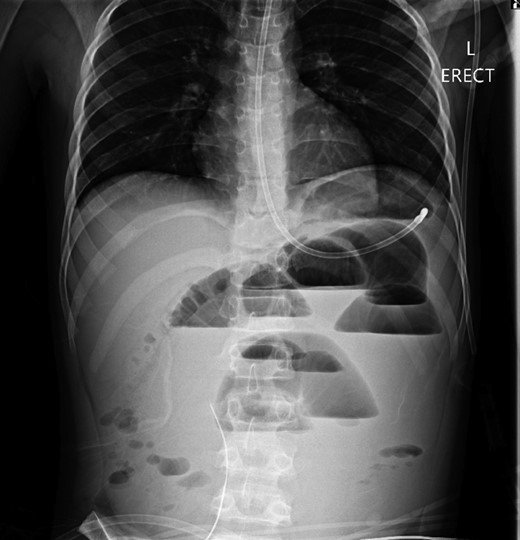

A 10-year-old boy presented unwell with generalized peritonitis after 3 days of abdominal pain, nausea and anorexia. He had a low-grade fever but all other vitals were within normal limits. Blood tests showed a raised white cell count of 16 × 109 with neutrophilia and raised C-Reactive Protein of 127 mg/l. Laparoscopy revealed generalized purulent peritonitis secondary to perforated appendicitis. Appendicectomy was performed and the appendiceal stump was secured. Lavage of the abdomen was performed with a minimum of four litres of warmed normal saline. Fluid was suctioned, an abdominal drain was placed and the pneumoperitoneum was deflated. By the second postoperative day, he developed an ileus with persistent vomiting (Fig. 1). This was managed conservatively with nasogastric intubation, bowel rest, electrolyte replacement and fluid therapy. It became clear by the fifth postoperative day that the patient had intestinal obstruction. On examination, he had a distended abdomen, with intractable nausea and vomiting. Blood tests revealed a normal white cell count and potassium remained at 3.3 despite supplemental intravenous replacement. Abdominal X-ray revealed a small bowel obstruction and he was taken back to theatre for an emergency laparotomy (Figs 2 and 3). A small bowel volvulus was discovered, with no evidence of intestinal malrotation. The volvulus involved a segment of distal jejunum to proximal ileum causing complete small bowel obstruction.

Erect chest radiograph on day 5 more consistent with small bowel obstruction.